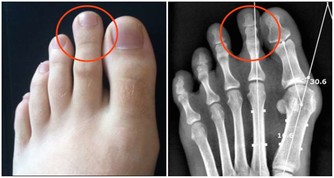

1、痔瘡

相信大家都聽說過痔瘡,但卻不知道痔瘡是怎麼形成的,痔瘡形成的因素有很多,一方面是飲食和不健康的排便,還有一方面就是衛生的原因。

我們都知道這個部位有很多的褶皺,最容易殘存一些臟東西,比如糞便,長時間的不清潔,這其中的細菌會在肛門處肆意的繁衍,最終形成痔瘡,出現便血,並且會有明顯的疼痛感,嚴重的情況可能會出現肛門脫出的情況。